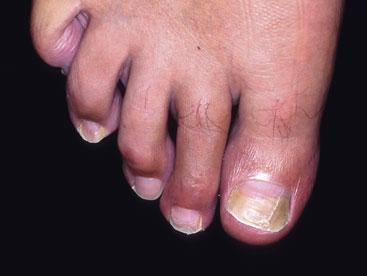

ONYCHOMYCOSIS (SUCCESSFULLY TREATED)

Fungal infection of the toenails is common. Generally the nail becomes thickened and hard to cut. The infection commences at the distal margin and will ultimately cause the whole nail to change if left untreated. Onycholysis may develop. Fungal infection of the skin of the feet may be present too (tinea pedis). Elderly people may develop thickened nails as a product of age rather than fungal infection. It is important to get a nail culture. In this case, the problem was treated with terbinafine and the normal nail has started to grow through.